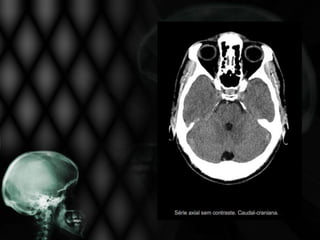

• Paciente de 78 anos, hipertenso, apresenta início súbito

de perda da força muscular à direita, com desvio de rima

bucal e sinais piramidais também à direita. É incapaz de

deambular e sua fala está arrastada e praticamente

ininteligível há 6 horas;

• Solicitou-se TC de crânio.

Não se visualiza nesta TC de crânio:

Edema cerebral

Sangramento na periferia do 4º ventrículo

Hipodensidade frontal direita extensa

Foco de sangramento no interior da área

isquêmica